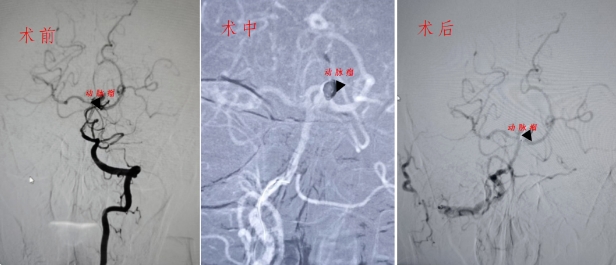

面對復(fù)雜的病情,沈衛(wèi)民主任和梁海波副主任迅速展開討論,為患者制定了周密的手術(shù)計(jì)劃。當(dāng)晚,楊伯伯即在介入手術(shù)室接受全麻下的主動(dòng)脈弓造影、全腦血管造影及經(jīng)導(dǎo)管顱內(nèi)動(dòng)脈瘤栓塞術(shù)。手術(shù)通過右腹股溝部動(dòng)脈穿刺進(jìn)行,術(shù)中利用微導(dǎo)管將彈簧圈精準(zhǔn)置入動(dòng)脈瘤內(nèi),有效防止了再出血的風(fēng)險(xiǎn)。